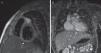

Imagen ecocardiográfica (plano paraesternal corto alto modificado a nivel de grandes arterias para valoración de raíz aórtica y arterias coronarias) en el que se objetiva la presencia de aneurismas gigantes en los segmentos proximales de las tres arterias coronarias principales (imágenes 1 y 2). Ecocardiografía de control en la que se evidencian trombos intraluminal en ADA y CD, manteniéndose la función cardiaca sistólica conservada (imágenes 3 y 4).

La detección inicial de las anomalías coronarias se realizó mediante ecocardiograma Doppler en su mayoría (fig. 1), excepto en un caso (paciente 4) en el cual en relación con un enfoque inicial atribuido a proceso viral, el diagnóstico inicial se realizó a través de TC torácica solicitada por infiltrados en ambos lóbulos superiores, identificándose alteraciones coronarias confirmadas en ecocardiografía. En todos los casos, en el estudio de imagen inicial se objetivó la afectación de más de una arteria.